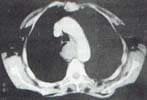

Se realizó TAC helicoidal con contraste que mostró un gran hematoma intramural en el esófago, que se extendería desde el esfínter cricofaríngeo hasta el hiato diafragmático, contenido por la pared del esófago y sin ruptura de la misma, sin sangre ni aire libre en el mediastino y con pequeños derrames pleurales bilaterales (figura 6).

Figura 6. Caso 4. (a y b). TAC helicoidal con contraste, en el que se observa un gran hematoma intramural espontáneo, de localización excéntrica, que se localiza sobre el contorno posterior y lateral izquierdo de la pared esofágica. Hay moderado efecto compresivo sobre la vía aérea en sentido anterior, particularmente sobre el bronquio fuente izquierdo.